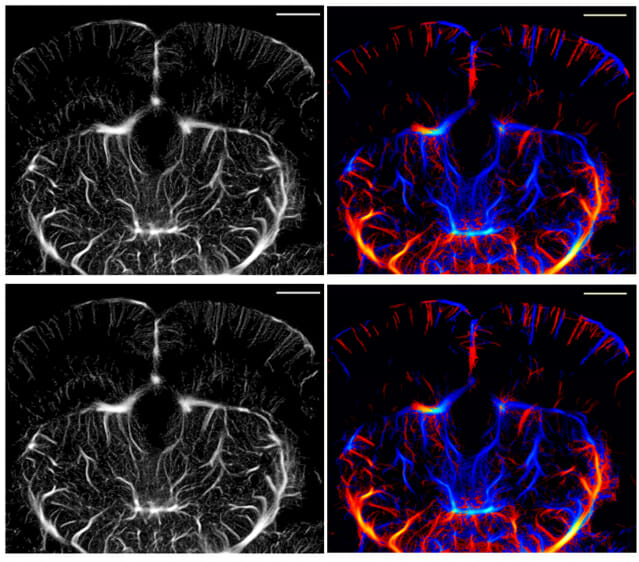

이를 보완하기 위해 개발된 기술이 ‘ULM(초음파 국소화 현미경)’이다. 혈액 속에 있는 초음파 조영제(마이크로버블)를 따라가며, 미세혈관의 구조를 초고해상도로 재구성한다. 기존 초음파로는 전혀 보이지 않던 머리카락 굵기의 수십 분의 1 수준의 혈관 지도를 그릴 수 있다.

DGIST 연구진은 이에, 초음파 신호 중 핵심 정보만 남기고 불필요한 데이터를 과감히 줄이는 새로운 분석 방식을 고안했다. 신호의 ‘유효 대역폭’을 약 67%로 줄이고, 혈관의 구조를 그리는 데 꼭 필요한 정보만 효율적으로 추출하는 ‘ULM-라이트(Lite)’ 방식을 새로 만들었다.

그 결과, 데이터 용량은 약 3분의 1로 줄였고, 영상 처리 속도는 30% 개선했다.

유재석 로봇및기계전자공학과 교수는 "장비교체 없이 기존 초음파 장비를 그대로 쓰면 된다"며 "그럼에도 화질은 기존과 거의 같다"고 설명했다.